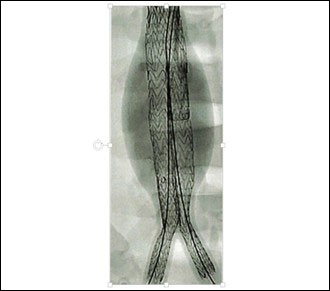

ステントグラフト内挿術

ステントグラフト内挿術は開腹手術に比較して創が小さく、患者様への負担が少ないと言われております。侵襲の低さに関して優位性が示されており、基本は全身麻酔で行いま。患者様の全身状態によっては局所麻酔での施行も可能です。新規の治療であるため長期的な成績に関しては集学的な治療を要します。デバイスは日々進化しており、同一デバイスでの長期成績が確認しづらいという難点もあります。今後さらなる発展が期待できる治療です。両側鼠径部に5cm程度の傷がつきます。開腹手術に比較して疼痛が少ないため、早期の離床が期待できます。